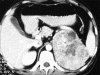

While different generations of assays have played important role in elucidating causes of different endocrine disorders, radiological techniques are instrumental in localizing the pathology. This statement cannot be truer in any disease entity other than endocrine hypertension. This review makes an effort to highlight the role of different radiological modalities, especially ultrasonography, computed tomography and magnetic resonance imaging, in the evaluation of different causes of endocrine hypertension.